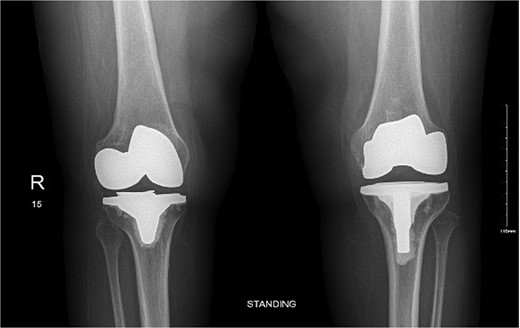

The case involves a 48-year-old obese woman with a body mass index (BMI) of 42, a known medical history of polio, and a baseline of bilateral knee hyperextension of 5º, who underwent bilateral staged TKA with posterior stabilized knee prosthesis in 2018 with a good functional level and outcome (Fig. 1).

Anteroposterior view of both knees post bilateral staged total knee arthroplasty.